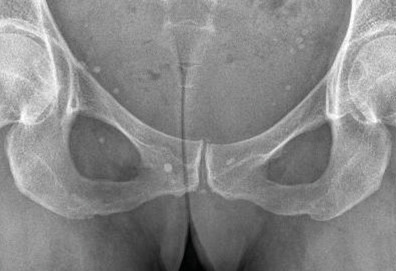

La forme pseudorhumatoïde est rare (5 %), simulant une polyarthrite rhumatoïde. L’arthrite chronique à PPC se présente comme une oligo- ou une polyarthrite, avec parfois des signes systémiques d’inflammation (élévation de la vitesse de sédimentation et de la protéine C-réactive [CRP]). La superposition d’accès aigus microcristallins est évocatrice de ce diagnostic. Il s’agit d’un diagnostic différentiel de polyarthrite rhumatoïde du sujet âgé ou de pseudopolyarthrite rhizomélique. Le diagnostic repose sur la mise en évidence des cristaux de PPC, même si les radiographies standard sont évocatrices. L’atteinte radiographique associe des calcifications des cartilages articulaires (fig. 7) et des fibrocartilages (fig. 8, 9, 10 et 11) [à rechercher systématiquement sur les radiographies de poignets, genoux et symphyse pubienne]. La mise en évidence d’une chondrocalcinose sur des radiographies standard renforce le diagnostic de rhumatisme à PPC mais l’absence de dépôts calciques ne l’élimine pas (la sensibilité de la radiographie standard étant imparfaite). L’échographie peut mettre en évidence des dépôts de PPC, qui apparaissent comme une fine bande hyperéchogène au sein des cartilages hyalins et comme des points scintillants dans les fibrocartilages ou dans la membrane synoviale. La sensibilité de l’échographie est bien supérieure à celle de la radiographie standard. Le scanner peut également mettre en évidence des dépôts calciques évocateurs, notamment au niveau du rachis ou du bassin qui sont plus difficilement explorés par les radiographies et l’échographie.

Les arthropathies liées à l’arthrose ou destructrices ont une fréquence qui augmente avec l’âge. L’arthrose associée aux dépôts de PPC touche en particulier les genoux, avec une symptomatologie chronique et/ou des accès aigus cristallins. Par comparaison avec l’arthrose idiopathique, l’arthrose avec dépôt de PPC serait à l’origine d’une symptomatologie plus inflammatoire, toucherait des articulations inhabituelles (radiocarpienne, carpienne, gléno-humérale, médio-pied et arrière-pied, cheville) et serait associée à plus d’ostéophytes et de géodes. Cette arthropathie dégénérative peut s’accompagner de lésions structurales sévères avec disparition rapide de l’interligne (arthropathies destructrices : hanches, genoux, poignets, coudes) mimant une ostéo­arthropathie nerveuse.